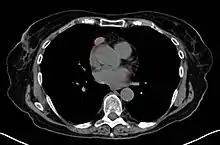

- CT scan

- Thymoma typically presents in the anterior/superior mediastinum